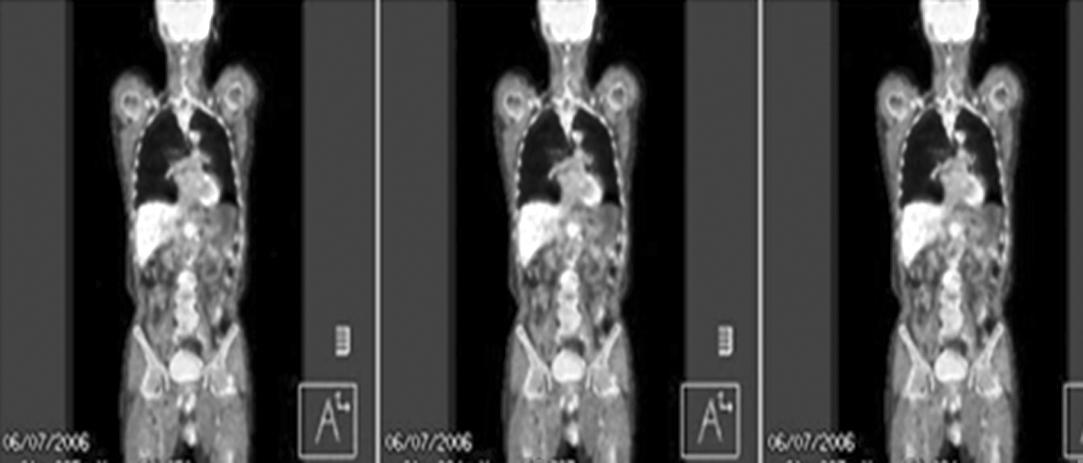

At 1 month after operation, the size of a retropancreatic node was increased and 18F-fluorodeoxyglucose (FDG) uptake was increased on PET-CT scan (Fig. 1). Therefore, radiotherapy was given to the draining abdominal lymph nodes and the metastatic node using 3D-CRT. Radiotherapy was given by three ports (anterior, posterior, and left) upto 45 Gy in 25 fractions from June to July 2006. On the dose-volume analysis, V30 of liver was less than 20% and V20 was 25%. Prior to irradiation, all the liver enzyme levels were within normal range (Child A) and chemotherapy was not added. During radiotherapy, CBC and liver function test were checked every week.

Fig. 1. 18F-fluorodeoxyglucose (FDG) PET/CT scan before abdominal irradiation. At 1 month after surgery, the size of the previously detected retropancreatic node was increased. The node also showed increased 18F-FDG uptake on 18F-FDG PET/CT scan (SUVmax=4.2). The arrows indicate the enlarged lymph node.